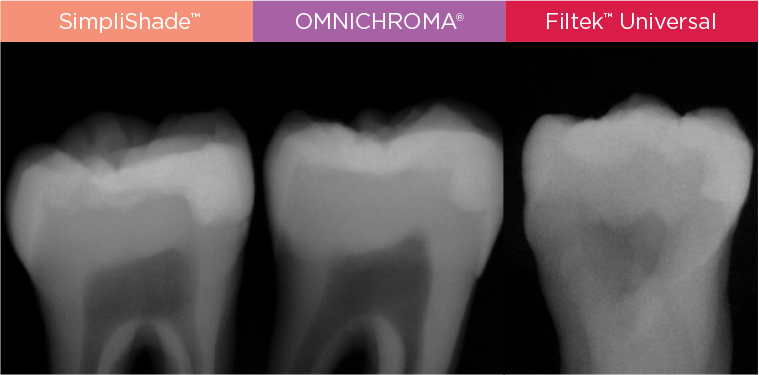

Uitstekende radiopaciteit

De hoge radiopaciteit van SimpliShade (300% AI) maakt de restauratie op een röntgenfoto zeer goed te onderscheiden van de tandstructuur.